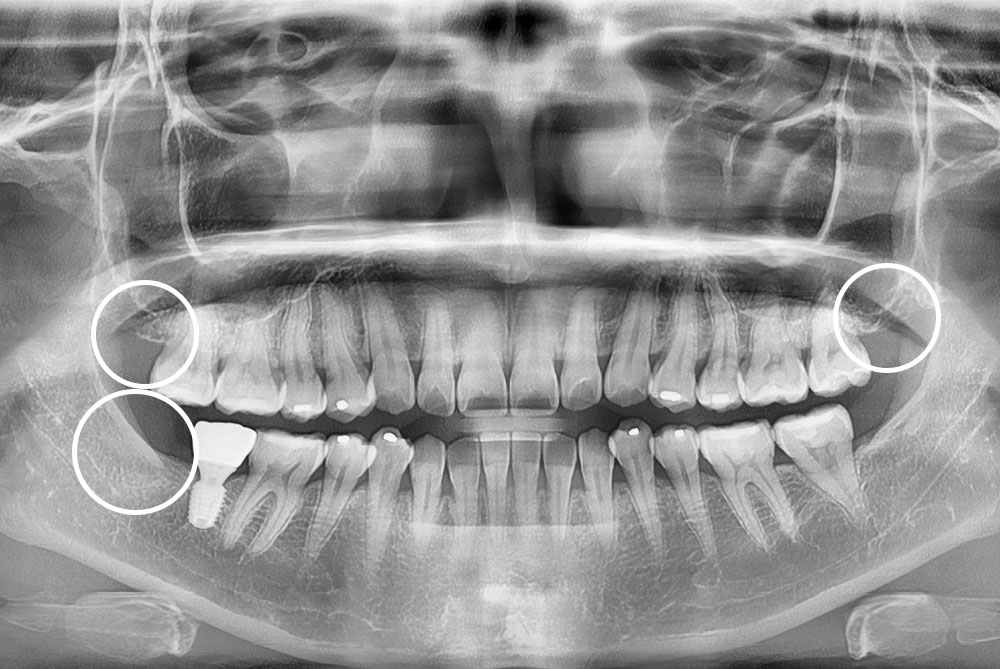

[사랑니] 매복 사랑니 발치

치료전 : 2018-11-17

세종치과는 구강악안면외과학 박사이신 원장님이 발치하는 치과입니다.